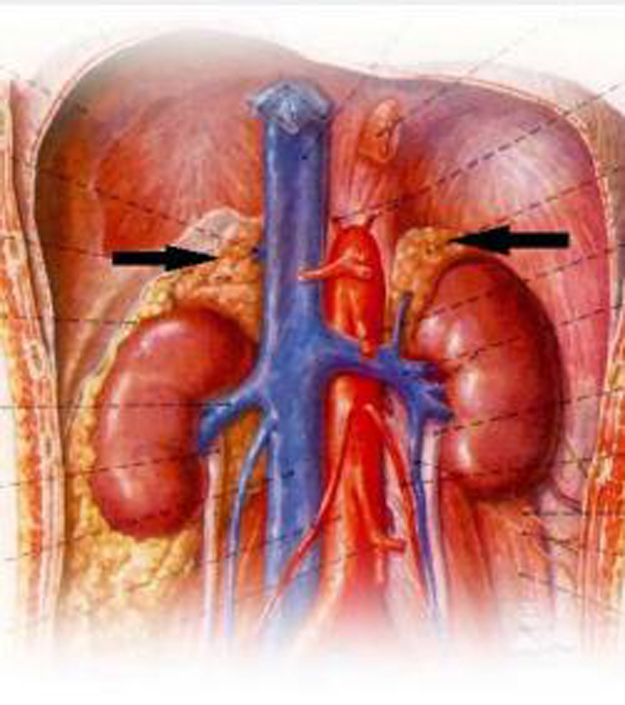

肾上腺是人体重要的内分泌腺之一,位于肾脏上方,左右各一,共重10~18克,左侧呈半月形,右侧为三角形。其由肾上腺皮质和髓质组成,通过分泌不同的激素,调节人体的生理功能,对维持正常的生理功能起重要的调节作用。一旦肾上腺的某一部位发生肿瘤,相应部位的激素就会过度分泌,即所谓“功能性肾上腺肿瘤”,进而引起一系列和激素过度分泌相关的临床症状,如:皮质醇症、醛固酮症、性激素分泌异常、嗜铬细胞瘤和恶性肾上腺皮质癌等。

(肾上腺人体解剖图,图示黑色箭头)